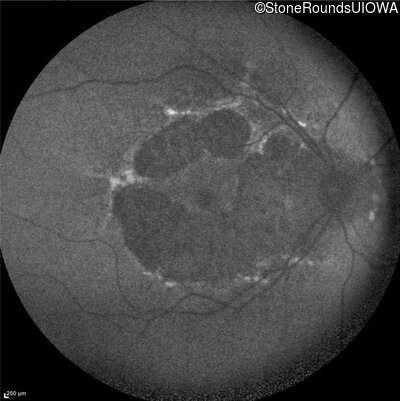

Age at visit: 59 years

This 59 year old woman first experienced defects in her mid peripheral field in the past year. Her hearing worsened in her 30's and she started wearing hearing aids at age 40. She was diagnosed with diabetes at age 39 and began using insulin at age 42.